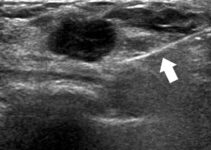

يمكن لطبيبك إجراء الخزعة بمساعدة جهاز الموجات فوق الصوتية. تستخدم هذه الآلة موجات صوتية عالية التردد لإنشاء صورة في الوقت الفعلي للعقيدة. هذا يسمح لمقدم الرعاية الصحية الخاص بك بتوجيه الإبرة إلى المكان الصحيح تمامًا. كما أنه يمنع الهياكل الأخرى من التلف. سيتم وضع مادة تشبه الهلام على رقبتك حيث سيتم استخدام كاشف الموجات فوق الصوتية.

يستخدم الفحص بالموجات فوق الصوتية الموجات الصوتية لإنشاء صورة لداخل جسمك.

يمكن للفحص بالموجات فوق الصوتية لرقبتك التحقق من وجود كتلة في الغدة الدرقية يمكن أن تكون ناجمة عن السرطان.